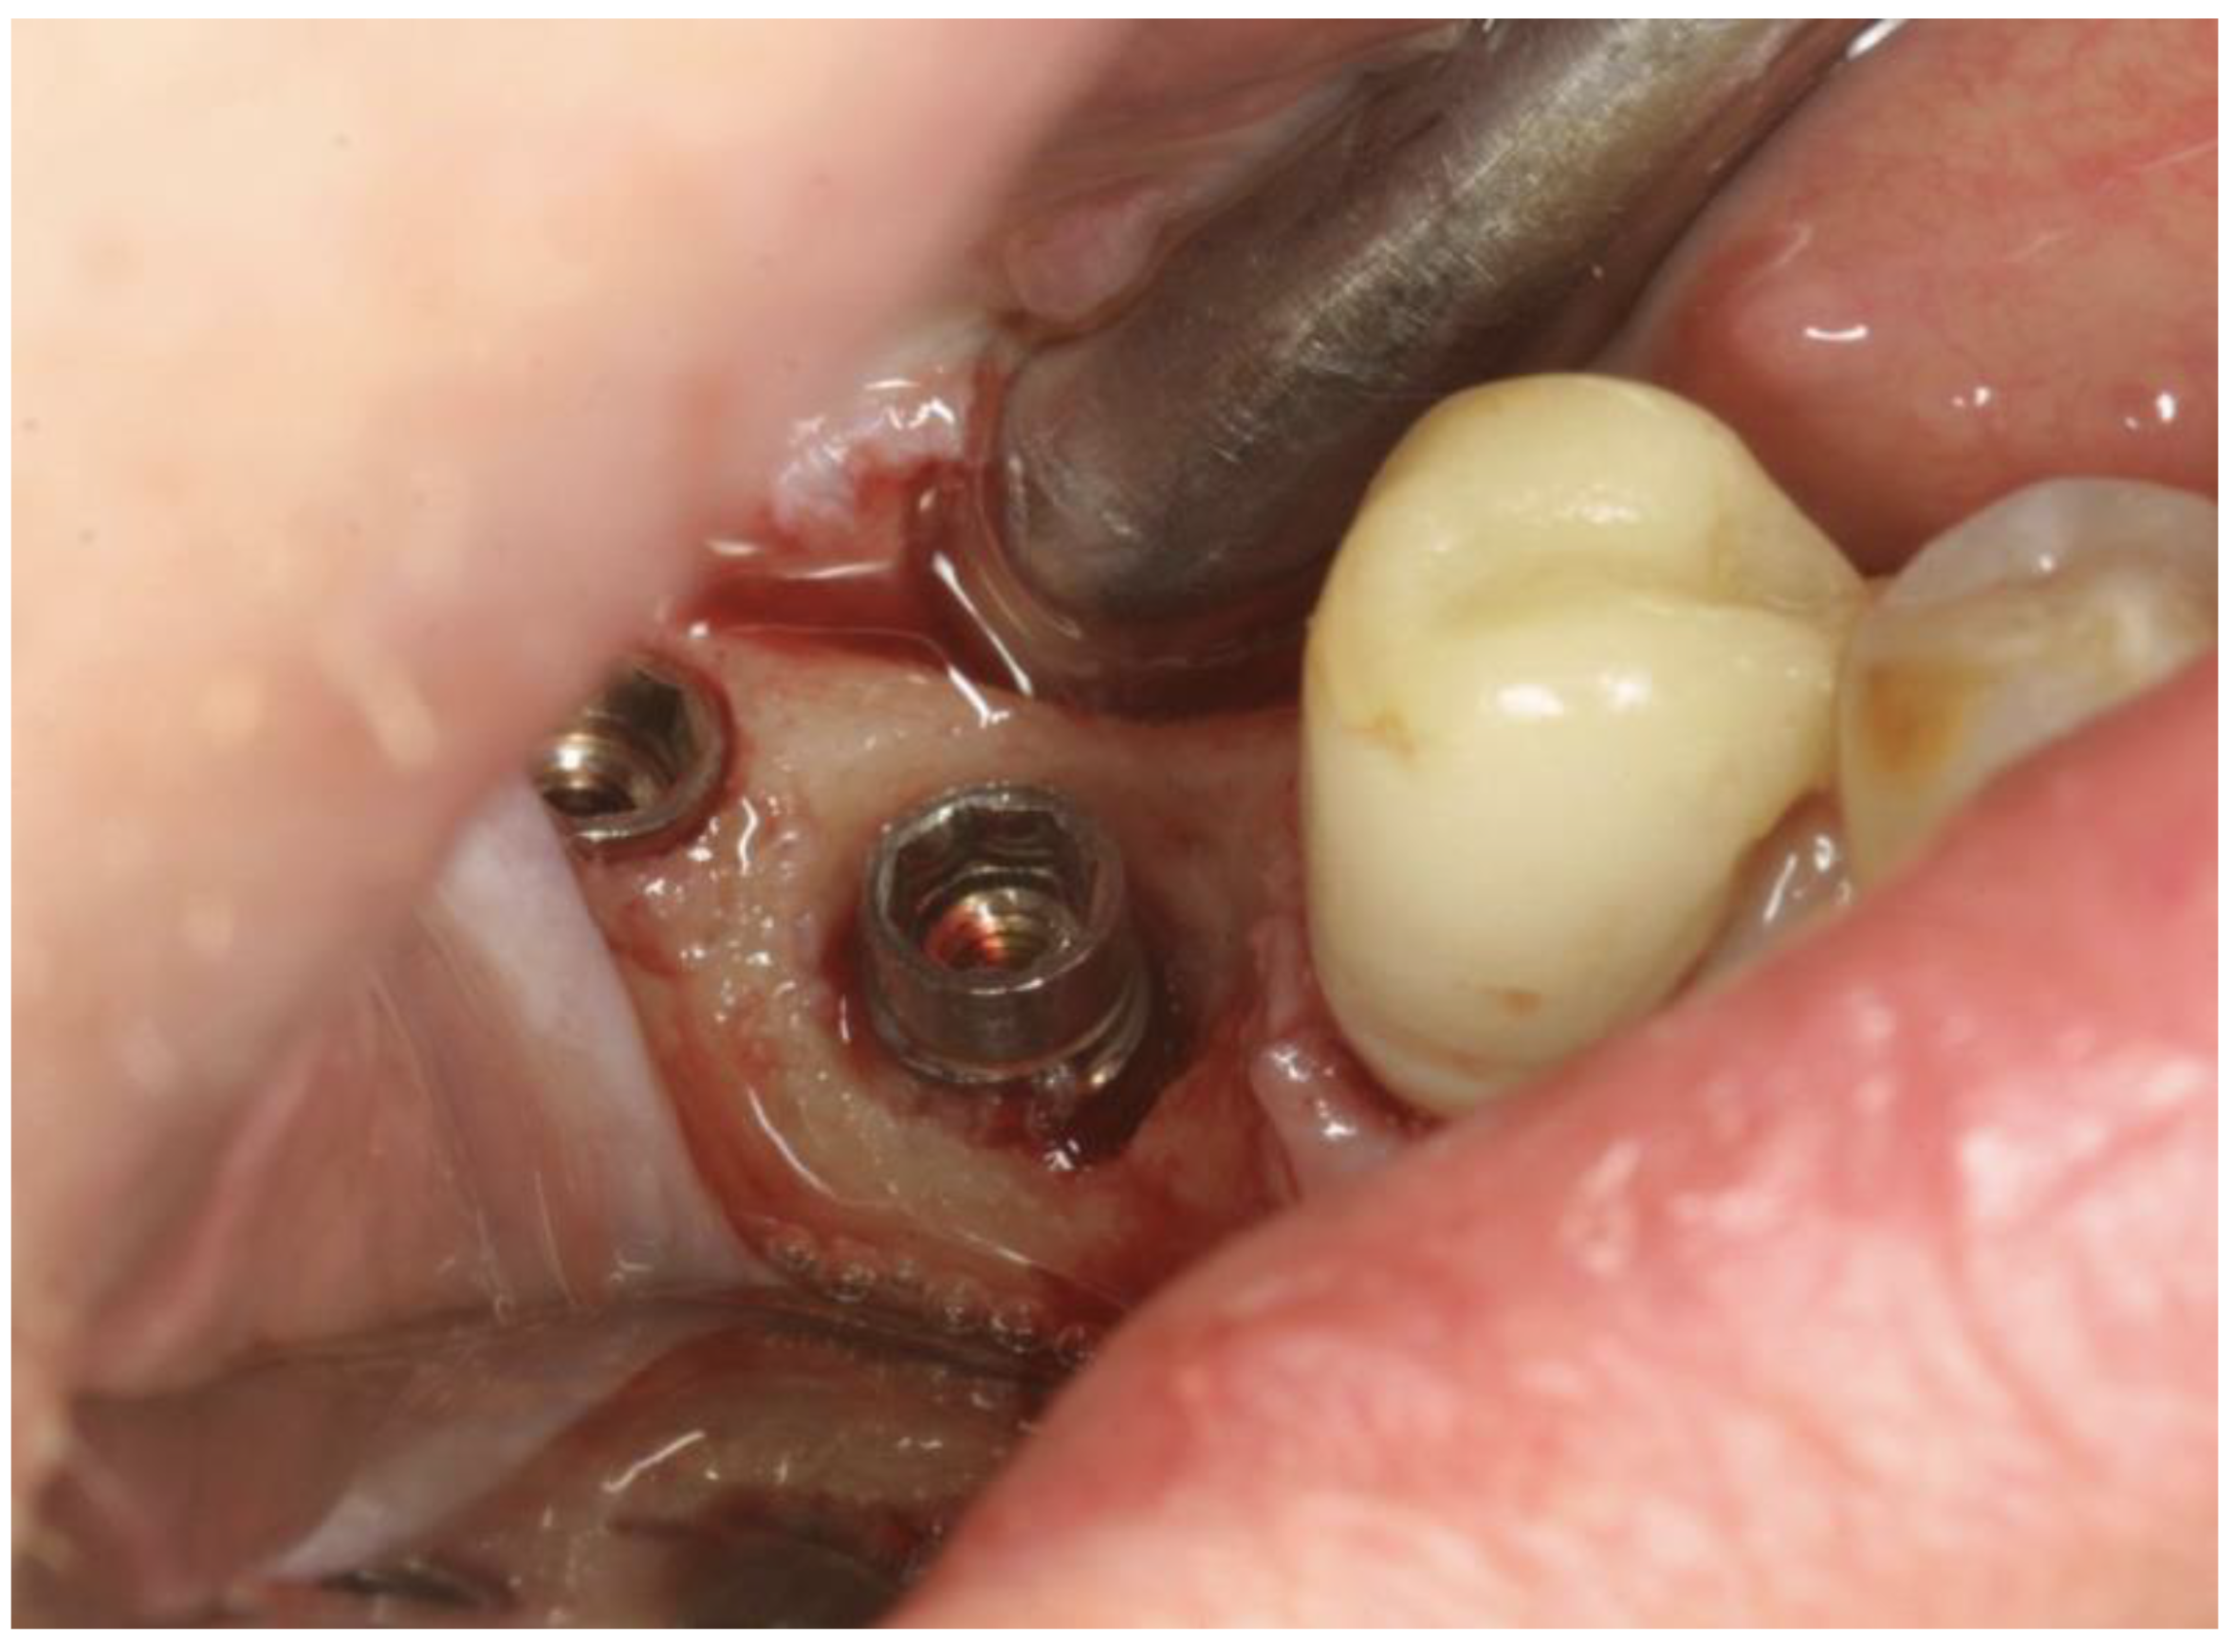

The OHLLT surgical procedure consists of (Figure 2 and Figure 3): local anesthesia; intrasulcular incision for a full thickness periodontal flap; mechanical instrumentation and removal of necrotic tissues with Gracey curettes; ultrasonic instrumentation for supra- and subgingival scaling combined with water–Betadine irrigation (5:1 ratio); air flow device with sodium bicarbonate powder (highly abrasive powder).

Figure 2. Full Thickness Flap.